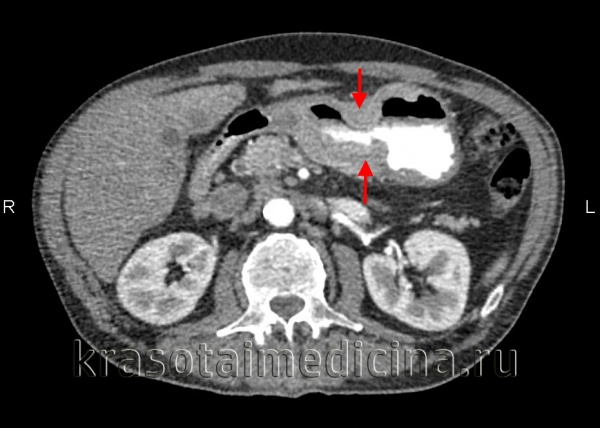

- КТ органов брюшной полости, грудной клетки и головы с внутривенным контрастированием — онкопоиск. Позволяет уточнить, поражены ли лимфоузлы, есть ли метастазы в других органах.